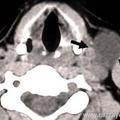

В диагностике боковой кисты шеи большое значение имеет КТ в режиме контрастирования, которая позволяет уточнить локализацию, топографические особенности ее расположения, размеры, плотность содержимого и состояние региональных лимфатических узлов.

На КТ шеи (слева) обозревается наличие инкапсулированной кисты, расположенная кпереди грудино-ключично-сосцевидной мышцы, на уровне подъязычной кости и щитовидного хряща. Форма кисты веретенообразная, размеры 3 см в переднезаднем и 2,5 см в поперечном измерение: вертикальный размер не менее 5 см. Внутри она имеет однородное кистозно-жидкостное содержимое (серозный мукоид) плотностью до 26 ед Н. Сонные артерии и внутренняя яремная вена расположены позади и медиальнее кисты - непосредственно прилегают к ее внутренней поверхности .